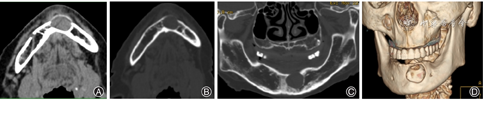

患者女性,68岁,因下颌骨体部无痛性缓慢膨胀肿物3年余,于2007年11月22日入院。查体:左侧下颌体部唇侧明显膨隆,表面黏膜及皮肤色泽正常,无瘘管及溃烂,触诊有“乒乓球”样感,有波动感,触痛不明显。实验室检查均正常。CT平扫示下颌骨体内见一大小约2.0 cm×2.0 cm占位,呈均匀软组织密度,未见钙化或坏死囊变征象,CT值约45 Hu,边缘光整、清晰,前缘轻度向外膨出,相邻骨壁吸收变薄,肿瘤相邻下颌骨前上骨皮质吸收近乎消失,冠矢状面重组像显示下颌骨局部类圆形骨质缺如,边缘光整,周边骨质无硬化,三维重建图像显示更加清晰(图2)。全麻下行左侧下颌骨肿瘤切除术,术中见肿物呈囊性,包膜完整,相邻下颌骨前上骨壁薄如纸样,肿瘤内含有豆腐渣样物质。大体标本:灰白灰红色囊性肿物一个,大小2.0 cm×2.0 cm×1.0 cm,囊壁厚0.1 cm,囊内含灰白豆渣样物。病理诊断:下颌骨表皮样囊肿。